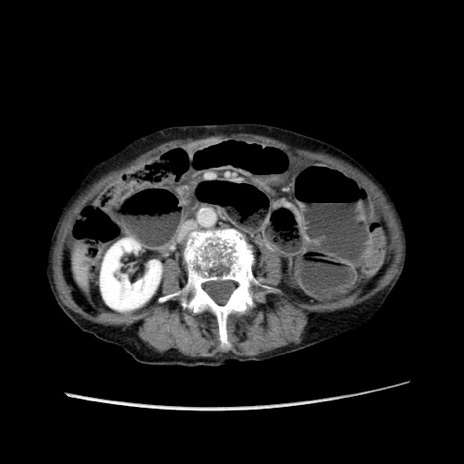

症例25(横断像)

【症例】80歳代女性

【主訴】胸のつかえ感

【現病歴】約9時間前に食後から胸のつかえた感じあり、嘔吐あり、来院。

【既往歴】胃癌(全摘)、胆摘、虫垂炎

【身体所見】心窩部に圧痛あり、反跳痛なし。

【データ】WBC 5700、CRP 0.05